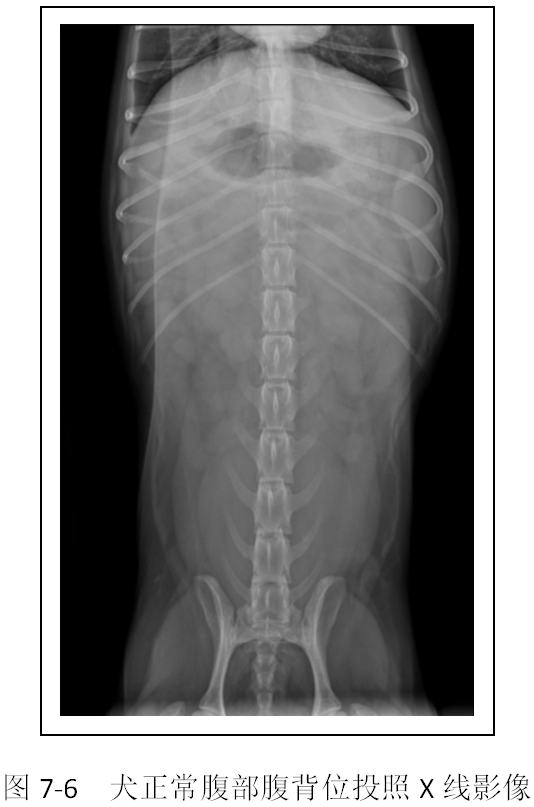

(2)识别X线影像中的胃、肠、肝脏、脾脏、肾脏、膀胱影像(图7-5、7-6)。

【拓展知识】腹部异常X线影像